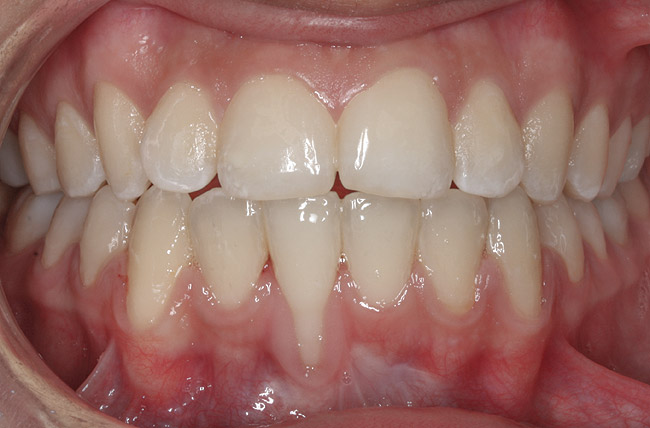

CASE 4 Fig 9. Post-orthodontic Miller Class II recession treated with surgical coverage only in spite of the incorrect inclination of the affected tooth. Clinical view immediately post-orthodontic treatment.

Figure 9

Fig 10. Same patient 5 months later showing worsening of the recession.

Figure 10

Fig 11. Same patient 1 year after connective tissue graft, showing partial root coverage.

Figure 11

It should be understood that this type of orthodontic movement requires reinsertion of a fixed orthodontic appliance in the lower arch for several months. Therefore, many of these patients reject retreatment. In such cases, surgical root coverage remains the only viable option; however, patients should be aware of the poor prognosis for complete root coverage and be prepared to accept compromised treatment outcomes (Figure 9 through Figure 11).